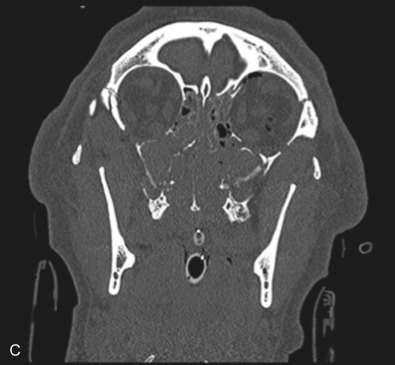

Le Fort II fractures are pyramidal in shape, involving the central portion of the midface while the lateral orbits and zygoma remain intact. The line of fracture extends bilaterally through the nasofrontal junction, medial orbital wall, inferior orbital rim, along the maxilla, through the dental alveolus anteriorly and posteriorly at the level of the maxillary tuberosity into the pterygoid plates ( Figs. 1.13.14 and 1.13.15 ). Only Le Fort II fractures violate the inferior orbital rim, causing the highest incidence of infraorbital nerve hypesthesia due to the proximity to the infraorbital foramen. Bones of the maxilla below the Le Fort II line of fracture can be intact, however they are often comminuted with other fracture patterns occurring in the Le Fort II segment. The force is typically delivered centrally at the level of the nasal bones, resulting in the separation of the central maxilla from the surrounding facial skeleton. Brain injuries are more frequent in central Le Fort II injury patterns.